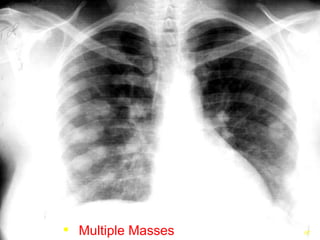

Multiple Masses

PULMONARY METASTATIC NODULES

• #75 Multiple lesions in the chest are typical for metastatic disease since the pulmonary capillary bed is often the first site metastatic lesions appear as they spread and embolize the pulmonary capillaries and grow in the new location.